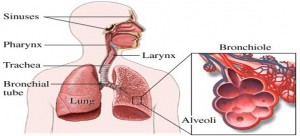

4. Респіраторні захворювання. Інфекції нижніх дихальних шляхів 5%

Антибіотики стали ефективною формою лікування, але і серед малозабезпечених верств населення їх важко отримати або занадто дорого.

7. Рак легенів, рак трахеї 3%

Причини: Куріння. На частку курців припадає майже 85% випадків смертей.